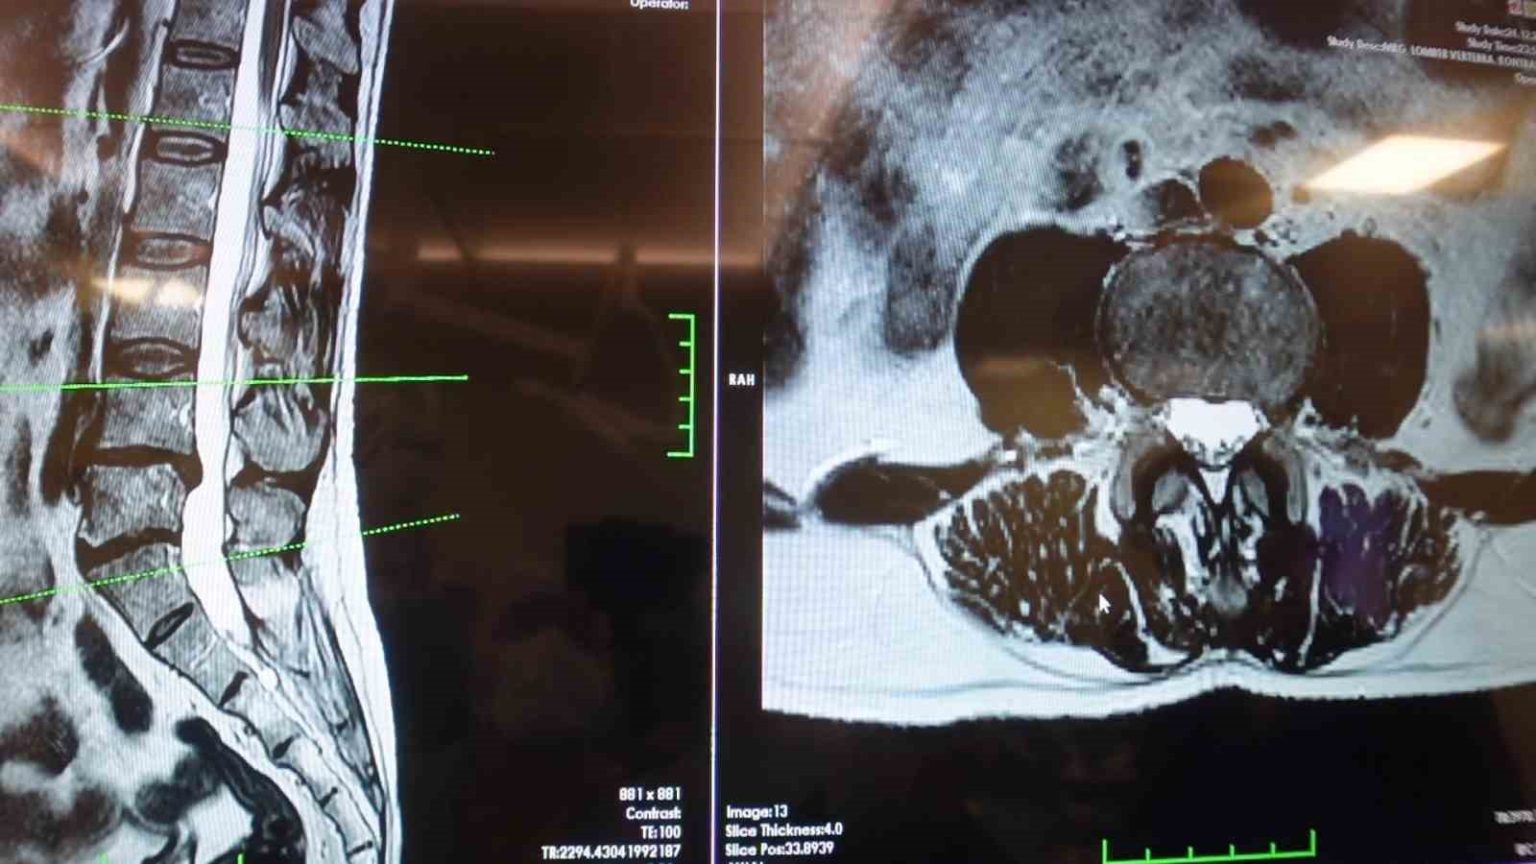

Elazığ Fırat Üniversitesi Hastanesi Beyin ve Sinir Cerrahisi Anabilim Dalı Başkanı Prof. Dr. Fatih Serhat Erol, bel fıtığı hastalığı hakkında açıklamalarda bulundu. Beyin ve sinir cerrahisi pratiğinde sık karşılaşılan hasta gruplarından birinin omurga hastaları olduğunu belirten Prof. Dr. Erol, “Boyun ve sırt omurlarının yanı sıra en çok bel bölgesiyle ilgili sorunlar görülüyor. Bel fıtığı önemli bir hastalıktır. Bel ağrılarının büyük bir kısmının bel fıtığından değil, mekanik bel ağrısından kaynaklanıyor. Mekanik bel ağrısının kaslar, eklemler, iskelet sistemi ve bu yapıları birbirine bağlayan bağların uzun süreli zorlanması sonucu ortaya çıkmaktadır. Bu durumun hastalarda şiddetli bel ağrısına neden olabilir. Mekanik bel ağrısının bel fıtığı ile karıştırılmaması gerekiyor. Bel fıtığına kıyasla mekanik bel ağrıları çok daha sık görülüyor. Bir diğer önemli hasta grubu ise omurilik kanal darlığı olan hastalardır. Bu hastalıkta dejeneratif süreçler sonucunda omurilik kanalında ve sinir köklerinin geçtiği kemik kanallarda daralma ve kireçlenme meydana geliyor. Bu durumun omurilik ve sinir köklerinde sıkışmaya yol açar. Hastaların ayakta dururken ya da yürürken bel, kalça ve bacaklara yayılan şiddetli ağrılar hissettiğini, yürüyüş mesafesi arttıkça oturup dinlenme ihtiyacı duyarlar. Tedavi sürecinin doğru tanıya göre belirleniyor. Bel ve bacak ağrısı şikayeti olan hastaların mutlaka bir beyin ve sinir cerrahisi uzmanına başvurması gerekiyor. Hastaların şikayetlerinin dinlenmesi, gerekli muayene ve tetkiklerin yapılmasının ardından hastalıkların birbirinden ayırt edilebildiğini ve buna uygun tedavi planının oluşturulur” cümlelerini kullandı.